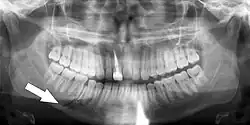

This injury involves the alveolar bone and may extend beyond the alveolus.[5][6] There are five different types of alveolar fractures:

- Communicated fracture of the socket wall

- Fracture of the socket wall

- Dentoalveolar fracture (segmental)

- Fracture of the maxilla: Le Fort fracture, zygomatic fracture, orbital blowout

- Fracture of the mandible

Trauma injuries involving the alveolus can be complicated as it does not happen in isolation, very often presents along with other types of tooth tissue injuries.

Signs of dentoalveolar fracture:

- Change to occlusion

- Multiple teeth moving together as a segment and are normally displaced

- Bruising of attached gingivae

- Gingivae across the fracture line often lacerated

Investigation: Require more than one radiographic view to identify the fracture line.

Treatment: Reposition displaced teeth under local anaesthetic and stabilise the mobile segment with a splint for 4 weeks, suture any soft tissue lacerations.